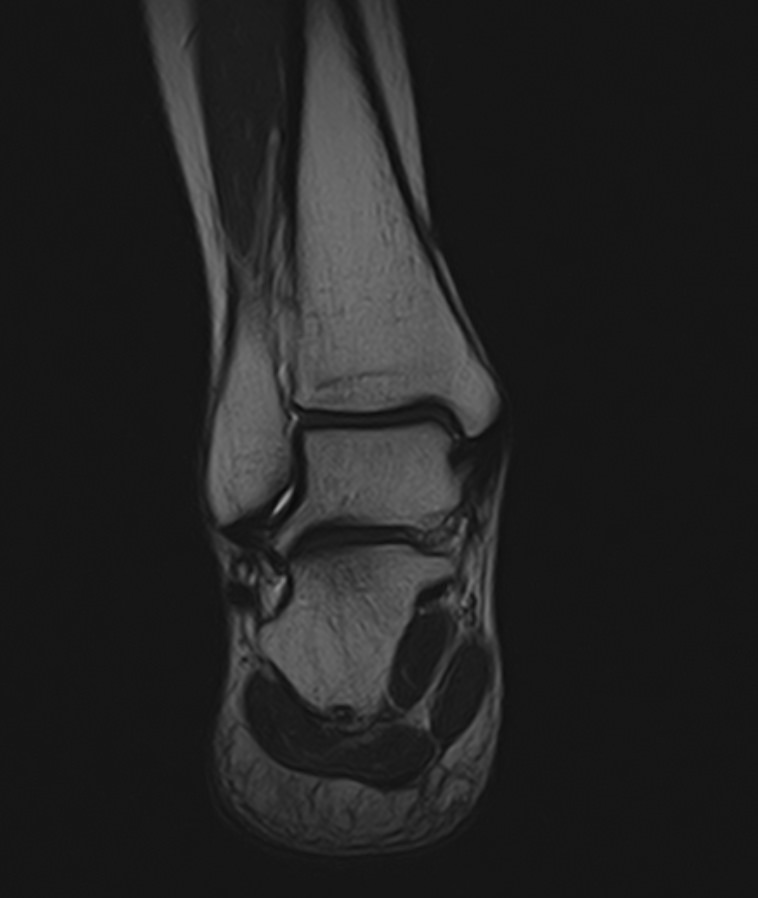

Наиболее точным и достоверным методом диагностики заболеваний голеностопного сустава является магнитно-резонансная томография. МРТ дает максимально полную информацию о состоянии всех анатомических структур сустава, включая костную ткань, сухожилия, связочный аппарат, нервные волокна и прилежащие мягкие ткани. Кроме высокой информативности метод МРТ является достаточно быстрой и безболезненной процедурой, при этом отличается безопасностью (нет рентгеновского облучения) и доступной ценой.

В нашей клинике можно пройти МРТ голеностопного сустава на современном высокопольном томографе экспертного класса TOSHIBA VANTAGE TITAN 1,5 Тесла, обладающего превосходной разрешающей способностью и создающего изображения с высокой детализацией и точностью.

Что покажет МРТ голеностопного сустава?

Снимки МРТ голеностопа показывают широкий спектр суставных заболеваний, включая:

• абсцесс и артрит, ахиллесов тендинит;

• трещины костей сустава и переломы;

• все разновидности костных инфекций;

• надрывы, растяжения и травмы сухожилий и хрящей;

• повреждение мышц голеностопа, остеонекроз (аваскулярный некроз);

• разрыв подошвенной фасции, дисфункции сухожилий;

• разрыв ахиллова сухожилия в области лодыжки;

• злокачественные и доброкачественные новообразования костных или мягких тканей;

• ущемление нервов, деформации, подагру, артроз;

• нарушение кровообращения в сосудистом русле сустава.